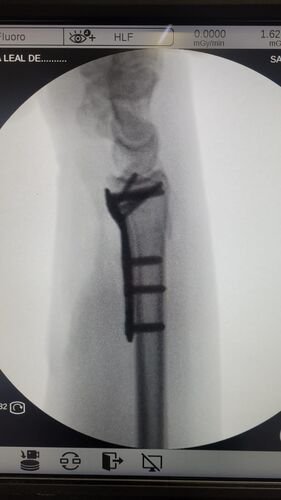

Meu nome e Isabella, mais conhecida como Snow, eu estava andando de muleta e a borracha dela saiu e eu tenho problema de equilibrio devido ao meu femur, bati o osso e piorou a situação, tive o radio do braço afetado e colocaram pino e deram um jeito de reverter porque eu ficaria com movimento do braço e mão comprometidos, tive traumatismo craniano porque bati a cabeça, esse ano eu já tinha sofrido um depois de um aparelho de raio x cair na testa mas fiquei sem sequelas na cabeça. Bom como muitos que me acompanham eu tenho uma condição rara entre mulheres que eu tenho os ossos do fêmur necrosados em mais de 75% desde 2022, eu sofri um acidente hoje andando de muleta, machuquei o fêmur, rosto, tivd que operar porque era uma emergência, não tenho muitas fotos pois estava internada mas tentei no SUS e não tinha pino de titânio,meu caso era de extrema urgência, eu to vendendo tudo e abrindo mão ate do meu apartamento pra cobrir a cirurgia e tenho ate final de setembro pra bater pelo menos 20 mil de meta, tenho inúmeras vakinhaa mostrando minha real doença autoimune e uma delas sendo rara que é osteonecrose bilateral do fêmur, o tratamento tá sendo todo particular mesmo sendo paciente do hospital das clínicas, ainda e difícil e nem sempre consigo as coisas, eu tento de todas formas é isso ainda pode me prejudicar na minha carreira, detesto pedir ajuda mas não tenho opção, a comunidade da minha área entre outros interesses sempre me apoiaram e infelizmente veio com humildade e de cabeça baixa pedir ajuda, faz tempo que tento recomeçar minha carreira desde o diagnóstico e nunca desisti dos meus sonhos e cirurgia

Vou deixar imagem atual do acidente abaixo e de algumas vakinhas anteriores